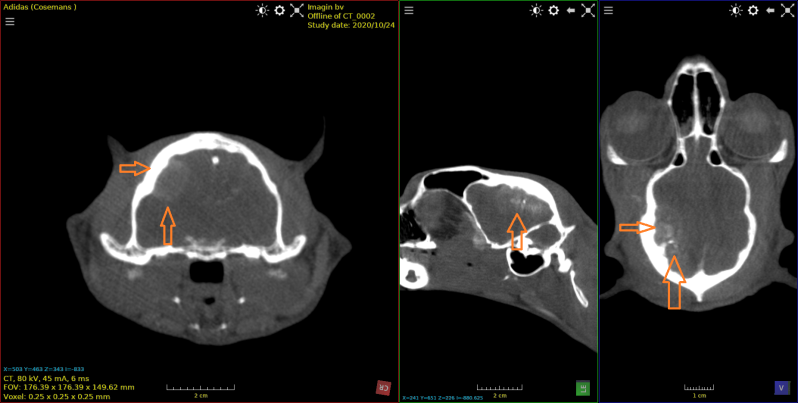

Kat van 11 jaar met bot tumor in de onderkaak